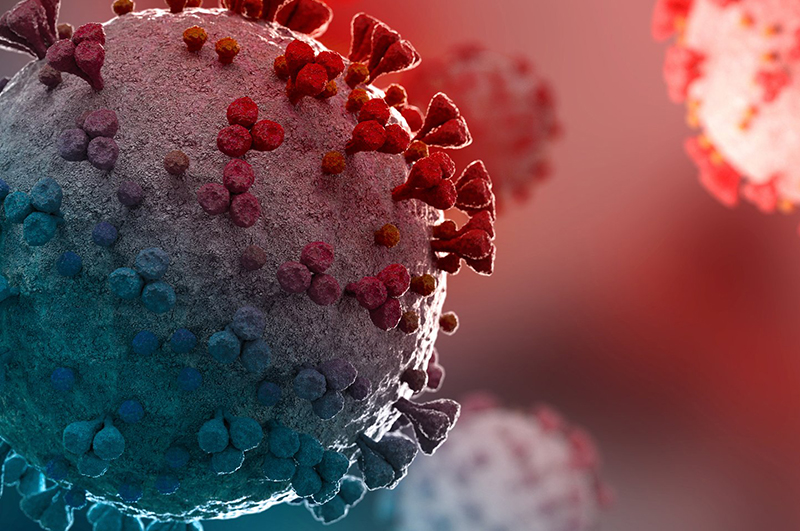

June 2024: Researchers from Mātai Medical Research Institute are conducting a pioneering "Tairāwhiti Study" to advance paediatric medicine. This initiative involves scanning over two dozen children to enhance understanding of anatomical variability across vital organ systems, including the brain, heart, lungs, and musculoskeletal system.

Recently, Henry McMullan from TVNZ 1 News visited Mātai Medical Research to report on their progress. The study employs cutting-edge imaging technologies and computational modeling to develop predictive models. Researchers aim to prevent disorders, enhance diagnostic precision, and personalize treatments, aiming to set new standards in child health.

"Our goal is to transform how we assess and treat children," emphasized study researchers, highlighting global potential for breakthroughs in child health.

Supported by the Auckland Bioengineering Institute, the pilot study has already shown promising outcomes. Collaborations with Tōnui Collab also aim to encourage local youth towards careers in science and technology.

For further insights, catch the segment featuring Henry McMullan on TVNZ 1 News.